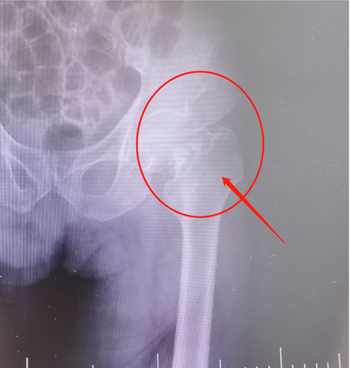

老大爷家属辗转打听到我院骨科现已成熟开展人工髋关节置换手术手术效果显著,遂慕名前来找到骨科主任邓颂波,请求救治其家属老大爷。邓颂波为老大爷进行详细的体格检查并结合影像检查结果诊断左侧股骨颈骨折

(术前)                          (术后)